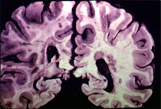

病理生理

長期高血壓可促使深穿支動脈血管壁結構變化,發生微小動脈瘤。目前普遍認為,微小動脈瘤或小阻力動脈脂質透明樣變性節段破裂是腦出血的原因。